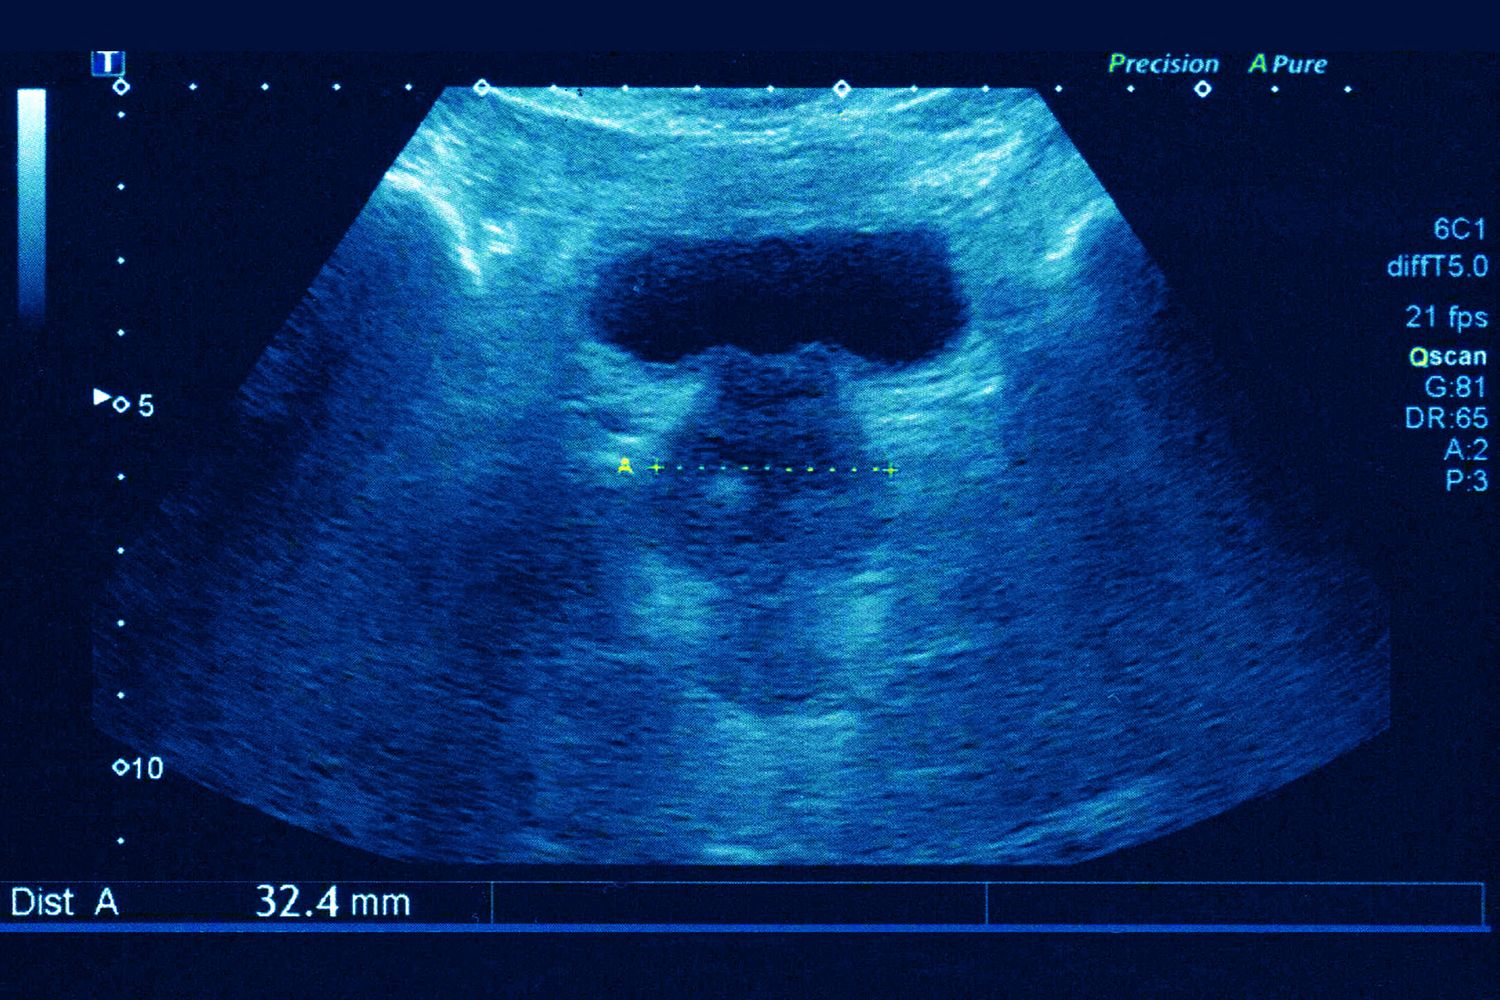

Ecografia della prostata

CAVALLINI JAMES / BSIP / AFP

- Ecografia della prostata